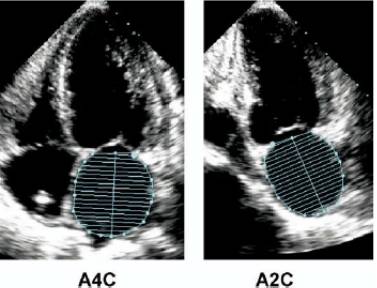

12、左心房容量测量

在临床实践中测量LA大小时,容量的测定优于径线的测量,因为它们能够准确地评价LA的非对称性重构。心血管疾病与LA容量的关系也比LA径线更为紧密。

在心室收缩末期(左心房径线最大时),用心尖四腔(A4C)和心尖二腔(A2C)双平面圆盘法(改良的Simpson‘s法)测量左心房(LA)容量。